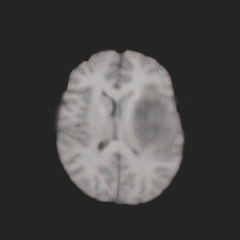

Multi-modal medical image completion has been extensively applied to alleviate the missing modality issue in a wealth of multi-modal diagnostic tasks. However, for most existing synthesis methods, their inferences of missing modalities can collapse into a deterministic mapping from the available ones, ignoring the uncertainties inherent in the cross-modal relationships. Here, we propose the Unified Multi-Modal Conditional Score-based Generative Model (UMM-CSGM) to take advantage of Score-based Generative Model (SGM) in modeling and stochastically sampling a target probability distribution, and further extend SGM to cross-modal conditional synthesis for various missing-modality configurations in a unified framework. Specifically, UMM-CSGM employs a novel multi-in multi-out Conditional Score Network (mm-CSN) to learn a comprehensive set of cross-modal conditional distributions via conditional diffusion and reverse generation in the complete modality space. In this way, the generation process can be accurately conditioned by all available information, and can fit all possible configurations of missing modalities in a single network. Experiments on BraTS19 dataset show that the UMM-CSGM can more reliably synthesize the heterogeneous enhancement and irregular area in tumor-induced lesions for any missing modalities.